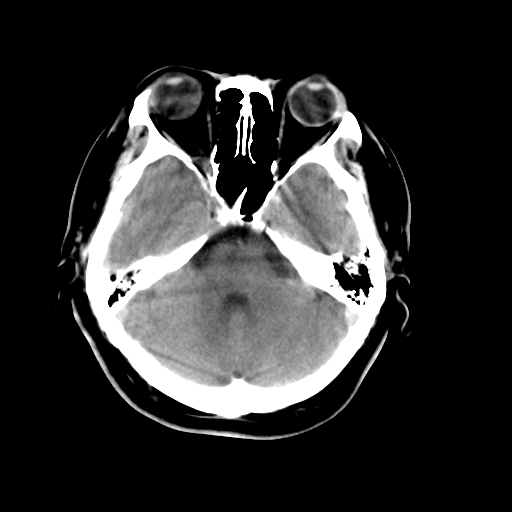

以下是引用liuyue在2008-4-28 13:34:00的发言:[br]右额叶条状高密度影,边缘清楚,周围未见水肿及占位.[br]考虑:血管畸形可能性大.[br]建议:强化ct扫描或mri检查.除外脑回钙化.

以下是引用论黑辩白在2008-4-28 12:53:00的发言:[br]右额叶局限性脑萎缩,右额叶见条状高密度影,建议mri进一步检查。[br][br][本贴已被 论黑辩白 于 2008-4-28 13:08:16 修改过]